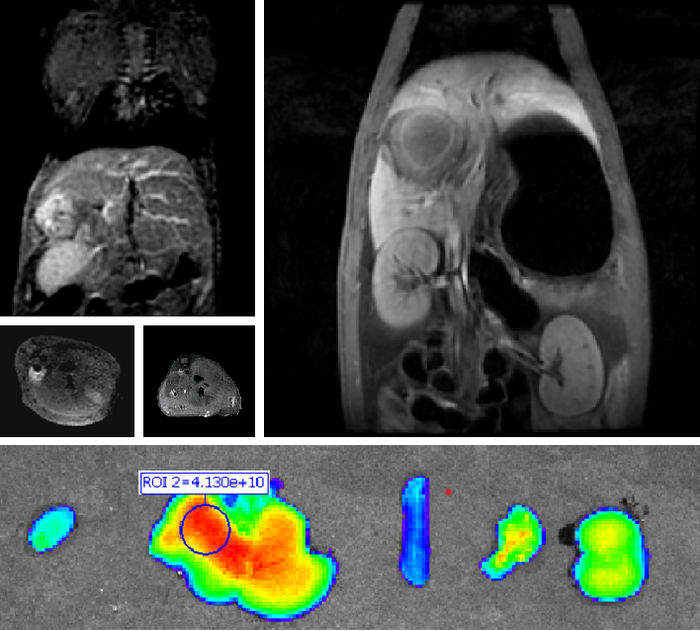

3、创新双模态造影剂(PL002)

普利制药自主研发的双模态造影剂PL002,已经获得美国FDA临床试验批件。PL002的研制首次提出通过整合磁共振技术,弥补现有荧光染料假阳性率高、透射深度有限等的短板,进而提升手术的精确性,降低手术过程中的风险,是全球首个获批临床试验的荧光/磁共振双模态造影剂。本项目预示着海南普利在造影剂领域的长期投入,并致力于开展独具特色的差异化国际化创新发展路径。

图 PL002获美国临床试验批件